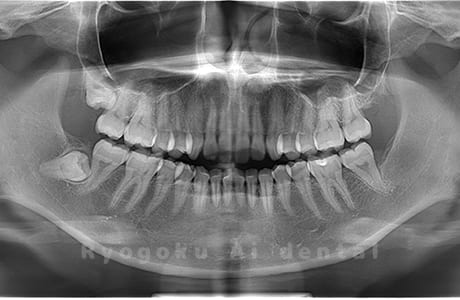

Case03

- 上顎、下顎の親知らず

- 上下4本の親知らずを抜歯したケースです。

<リスク・副作用>

手術後は痛み、腫れ、痺れなどの副作用が生じる場合があります。